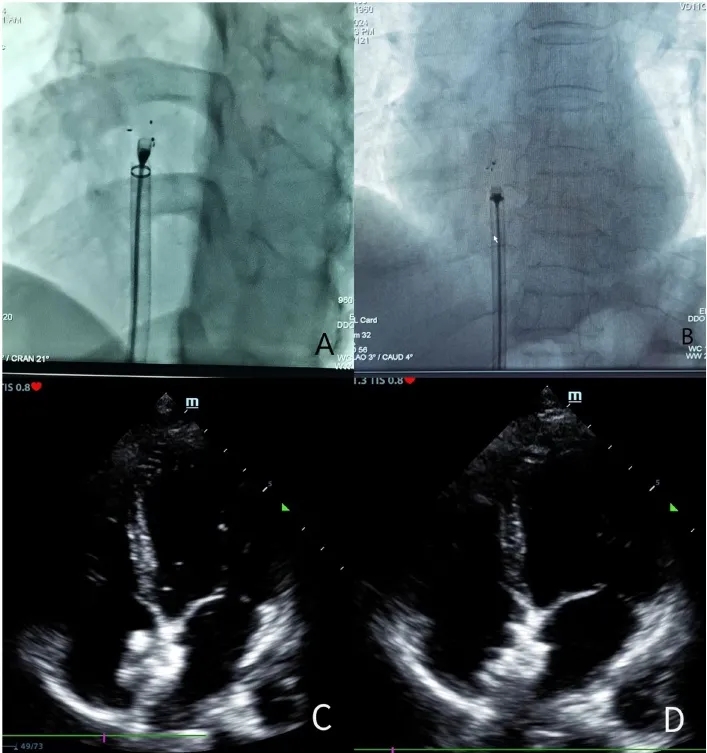

术前15分钟静脉给予预防性抗生素。手术过程中,患者平躺在手术台上。使用利多卡因对右侧腹股沟进行局部麻醉。选择右侧股静脉路径,插入6F静脉鞘。根据患者体重(80-100 IU/kg)给予肝素(18)。将其更换为8.5F Swartz鞘管,并送至上腔静脉。鞘管尖端指向房间隔。当出现落空感时,尝试将导丝通过卵圆孔送入左肺静脉。然后,送入加硬导丝和10F-16F输送鞘,并沿输送鞘送入封堵器。展开左伞盘后,后撤鞘管;随后展开右伞盘。确认封堵器无移位后,进行后续操作。对于可降解封堵器,在超声确认封堵器贴合于左心房间隔后,牵拉成型线尾部使封堵器锁定成型并紧密贴合房间隔,随后进行后续操作(图1)。手术中使用的可降解封堵器均来自上海形状记忆合金材料有限公司。

图1.(A)在X线透视下释放可降解卵圆孔未闭封堵器前;(B)在X线透视下释放可降解卵圆孔未闭封堵器后;(C)术中经胸超声心动图(TTE)释放可降解卵圆孔未闭封堵器前;(D)术中经胸超声心动图(TTE)释放可降解卵圆孔未闭封堵器后。